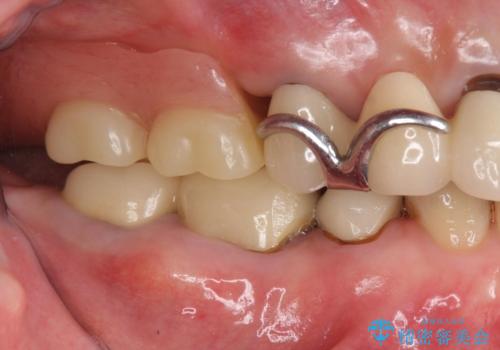

- 他院で右下小臼歯が保存不可能と言われ来院。当院の判断でも残念ながら抜歯となり、欠損部は抜歯後ブリッジにしました。右下奥2本が連結されていたため、そこは各々切り離した形で被せ物のやり替えも行っています。

抜歯後3か月ほど仮歯で生活していただき、欠損部の歯肉の状態が安定してからブリッジを入れています。